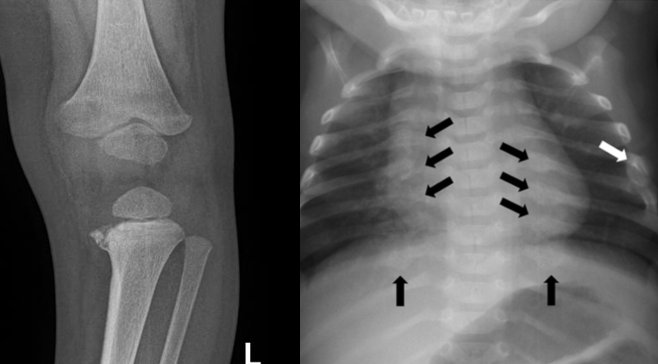

Child Abuse (Non-Accidental Trauma—NAT) Fractures

Occurs most often in children under 3 years of age.

Median age is 7 months.

Common Fractures in NAT (Non-Accidental Trauma):

Femur, humerus, and skull fractures are the most common sites.

Clavicular fractures and spiral fractures of long bones in non-ambulatory children.

Bucket Handle Fracture:

Occurs when an adult grabs, twists, or shakes a child’s limb in frustration.

Shaking the child, causing the limbs to move back and forth, can also cause a bucket-handle fracture.

It is difficult to sustain this injury from accidental causes, such as a fall.

Posterior rib fractures (due to compressive squeezing).

Multiple fractures, especially if they are in different stages of healing.

Be suspicious of any injury that does not fit the stated cause of injury.

Delay in seeking treatment.**